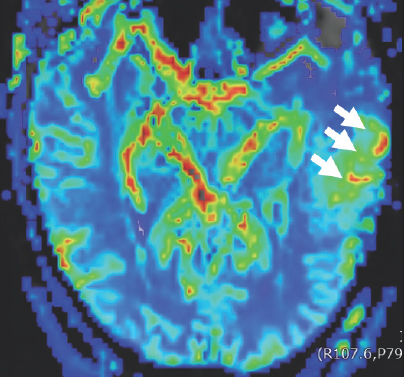

Dark blue, green, light blue, orange, red, and yellow colors are scattered within a blue boarder. Three white arrows point to a green blob on the right side of the image that has two sickled ovals that are red, orange, and yellow in color.

FIGURE 2.3 Brain MRI before surgery. Further exploration with advanced perfusion MRI demonstrates that this mass contains areas of moderately increased cerebral blood volume (CBV) (white arrow) suggestive of a tumor.